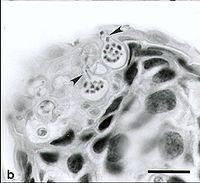

可見到兩個孢子囊中有多個游離孢子。壺菌病是於1993年在昆士蘭已死或正在死亡的蛙類中發現。研究發現這種病自1978年已經遍布整個澳大利亞。在非洲、美洲、歐洲、紐西蘭及大洋洲都有發現。在澳大利亞、巴拿馬及紐西蘭,正當蛙類的數量下降時,壺菌突然出現及擴散開來。不過,壺菌可能只一個普通的真菌,因它們的毒性及擴散程度,到最近才被發現及認識。在澳大利亞的東岸、阿德萊德、西澳州的西南部及金伯利曾有它們的蹤影。

蛙壺菌的游離孢子相信最先進入兩棲類的皮膚,並迅速長出孢子囊,再產生新的游離孢子。隨著新的游離孢子再次在主體生長,主體因而感染壺菌病。感染了壺菌病的蛙類會有形態上的改變,包括腹部皮膚會變為紅色、後肢抽搐、身上積聚脫下的皮、腳部及其他部份的淺表皮脫落、皮膚出現輕微粗化及細小的潰瘍或出血。患者行為上表現無力、不能找到遮蔽處、不能逃跑、失去正常的反射作用及出現不正常的姿勢。